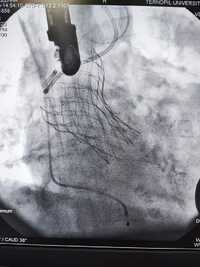

У Тернопільській обласній клінічній лікарні вперше виконано транскатетерну імплантацію аортального клапана. Про це повідомили на фейсбук-сторінці лікарні.

Команда лікарів із відділень інтервенційної радіології, кардіохірургії та трансплантології Тернопільської обласної клінічної лікарні та відділення мініінвазивної кардіохірургії клініки для дорослих центру дитячої кардіології та кардіохірургії міста Київ прооперували двох пацієнток, у яких було критичне звуження аортального клапана та важка супутня патологія.

Суть операції полягає в тому, що на працюючому серці виконується невеликий отвір, на якому через трубку-катетер по провіднику вводиться згорнутий клапан. Позиціонування контролюється як рентгенівським зображенням, так і черезстравохідним ультразвуковим датчиком.

Після імплантації хірург затягує вузол навколо отвору і вшиває рану. Крововтрата є мінімальною. Це новий рівень кардіохірургічних операцій, кажуть медики.